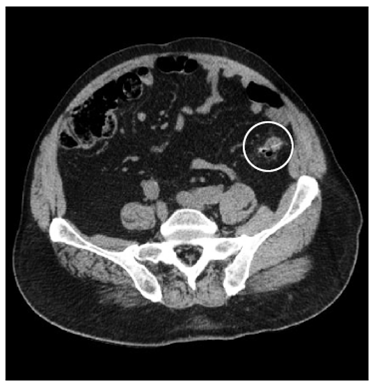

En la TC se observó un cuerpo extraño (espina de pescado) incrustado en el tercio distal del colon descendente, con escasas burbujas de gas libre y diverticulosis del colon (figura 1).